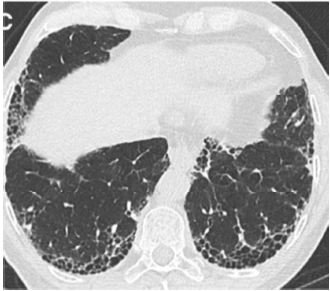

O paciente traz uma tomografia prévia solicitada pelo médico de família e representada nas imagens a seguir.

American Journal of Respiratory and Critical Care Medicine. Volume 198 Number 5 September 1 2018 (com adaptações).